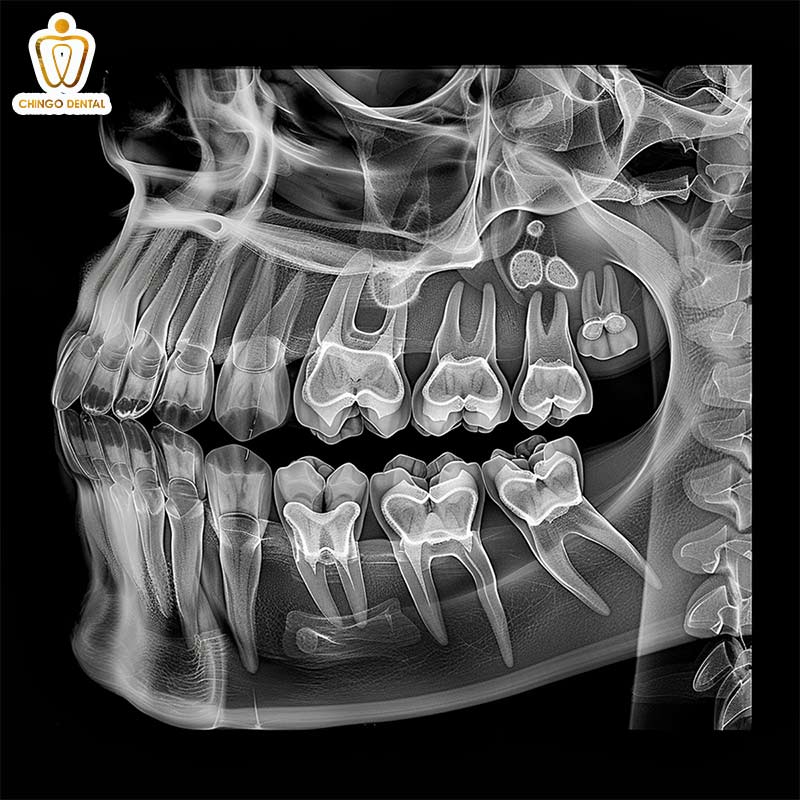

Công nghệ CT Cone Beam: Bản đồ 3D sắc nét

Đây là đỉnh cao của công nghệ chẩn đoán hình ảnh hiện nay. Không còn là những tấm hình phẳng, CT Cone Beam tái hiện lại toàn bộ cấu trúc hàm răng của bạn dưới dạng không gian 3 chiều (3D). Chụp X-quang răng 3 chiều giống như một bản đồ vệ tinh siêu thực. Cho phép bác sĩ “xoay” hàm răng trên màn hình để nhìn từ mọi góc độ.

Đặc biệt, nếu bạn đang băn khoăn trồng implant có chụp X-quang răng được không. Thì đây chính là kỹ thuật bắt buộc mà các bác sĩ nha khoa Hà Nội luôn chỉ định trong mọi ca phục hình implant. Để đảm bảo trụ Implant được đặt vào vị trí an toàn và bền vững nhất.